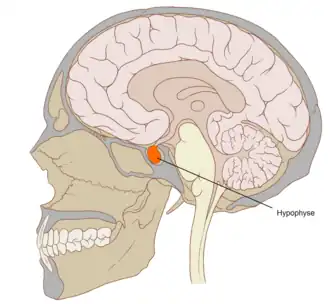

| Posição da glândula pituitária (ou hipófise) | |

A apoplexia pituitária é um enfarte ou uma hemorragia súbita da glândula pituitária, na presença dum adenoma pituitário. O sintoma inicial mais comum é uma súbita dor de cabeça, muitas vezes associada a um rápido agravamento do campo de visão e visão dupla causada pela compressão dos nervos que correm em estreita proximidade com a glândula. Normalmente, em muitos casos, pode-se constatar sintomas agudos causados por falta de secreção de hormonas essenciais, predominantemente insuficiência adrenal.[1]